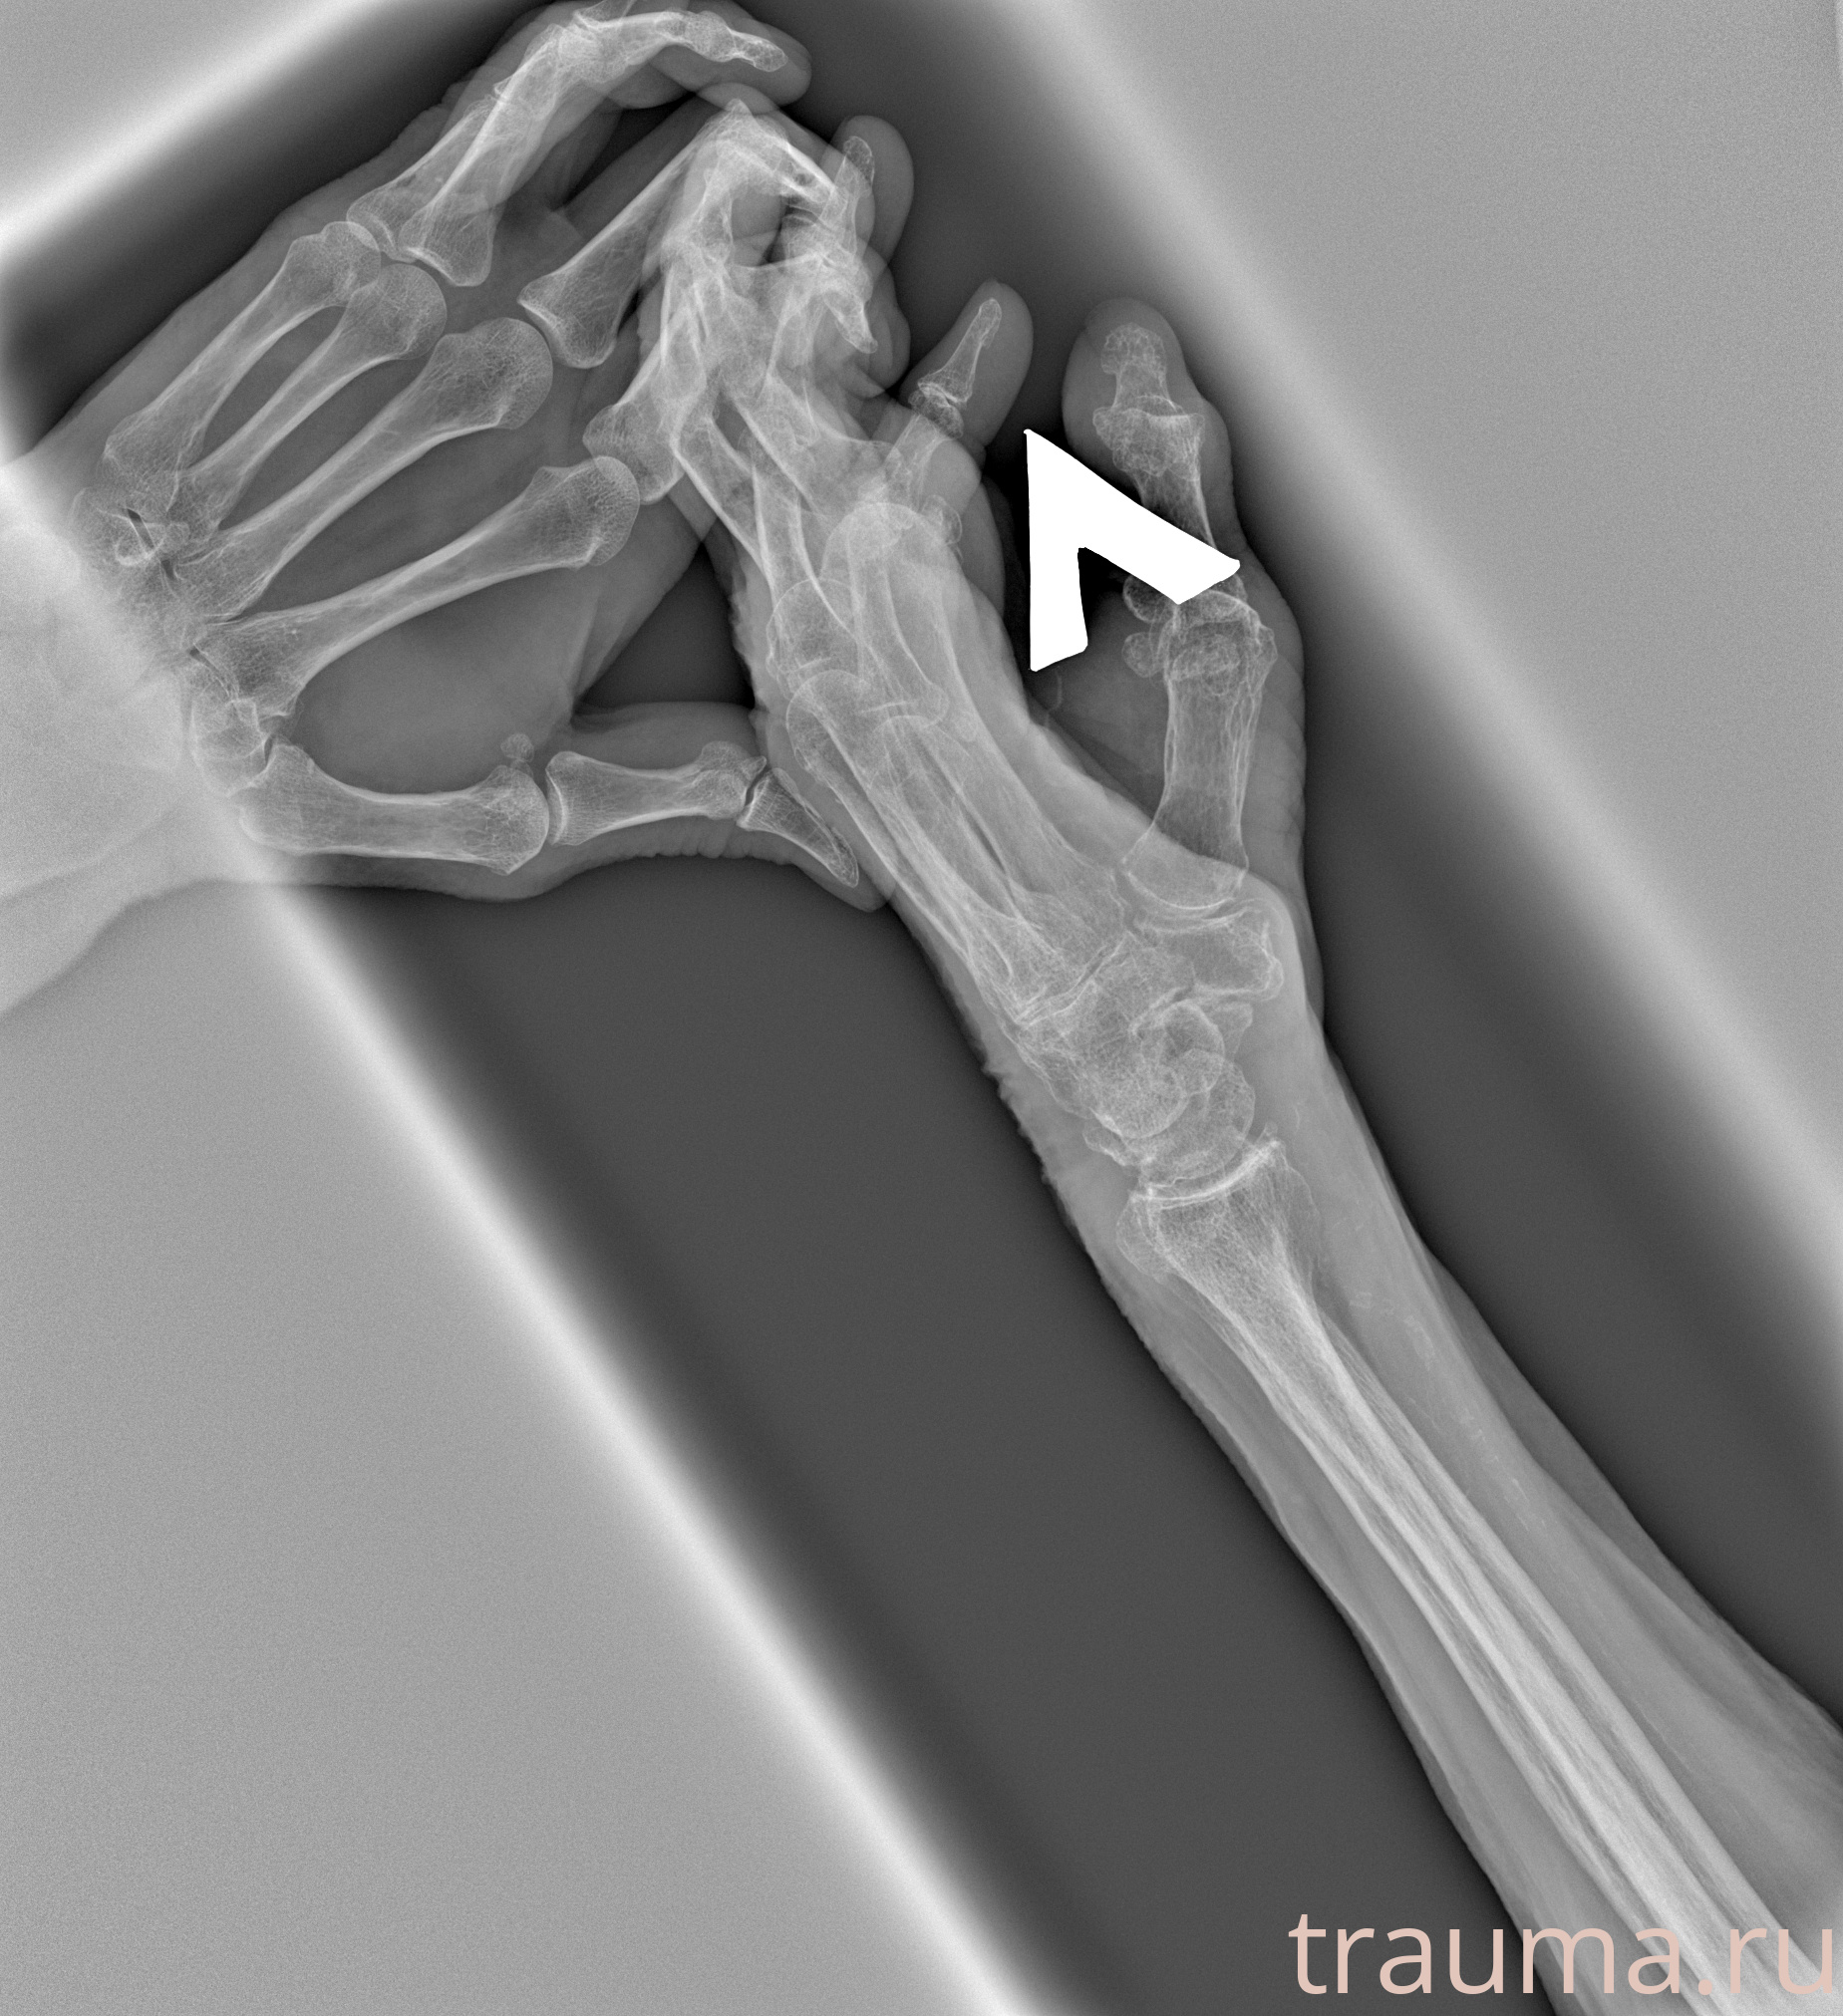

Рентгенограммы

Рентген на дому: по вашему адресу приезжает врач-рентгенолог, травматолог-ортопед с мобильным рентгеновским аппаратом, проводит диагностику травмы или заболевания, делает необходимые рентгенограммы, дает рекомендации по дальнейшему лечению. Получить качественные снимки в домашних условиях возможно благодаря уникальной методике, разработанной МосРентген Центром для института  Склифосовского